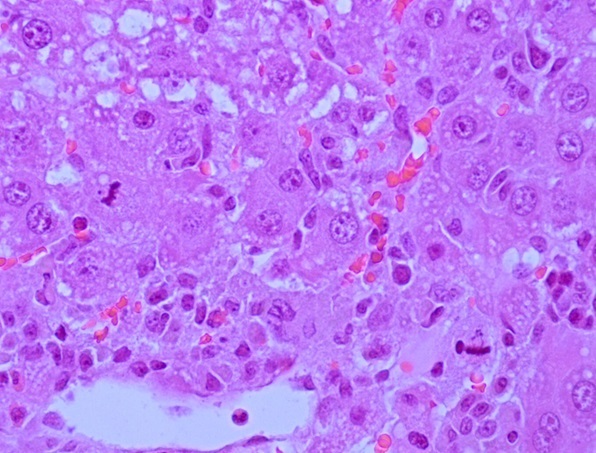

Введение. Проведена экспериментальная оценка влияния ССL4 и трансплантации клеток фетальной печени (КФП) на степень деградации и процессов репарации ДНК в клетках печени крыс, используя метод щелочного гель – электрофореза единичных клеток.

Материал и методы. Острое токсическое поражение печени крыс моделировали однократным внутрижелудочным введением крысам – самкам линии Вистар препарата CCl4 в масляном растворе в дозе 3000 мг/кг. В качестве протекционного средства использовали суспензию КФП плодов крысы 19 ДР. Для количественной оценки, степени повреждения ядерной ДНК клеток печени, применяли метод щелочного электрофореза единичных клеток (ДНК-комет) на 1, 3, 5, 7 и 16 сутки эксперимента.

Результаты. Внутривенное введение КФП через 6 часов после воздействия тетрахлорметана активировало процессы репарации ДНК в гепатоцитах крыс на 5 – 7 сутки, что приводило к снижению интенсивности повреждения ядерной ДНК. Тенденция к уменьшению числа неповрежденных гепатоцитов сохранялась и на 16 сутки эксперимента, при этом усиление репаративных процессов после введения КФП реализовалось в достоверном сокращении количества гепатоцитов с высокой интенсивностью повреждения ядерной ДНК.

Заключение. Использованный в наших экспериментах метод щелочного гель – электрофореза единичных клеток (ДНК-комет) позволил количественно оценить степень повреждения генома и его репарацию. Выявленные позитивные результаты свидетельствовали о протекторной роли КФП на структуру ДНК клеток печени крыс, после острого воздействия CCL4.